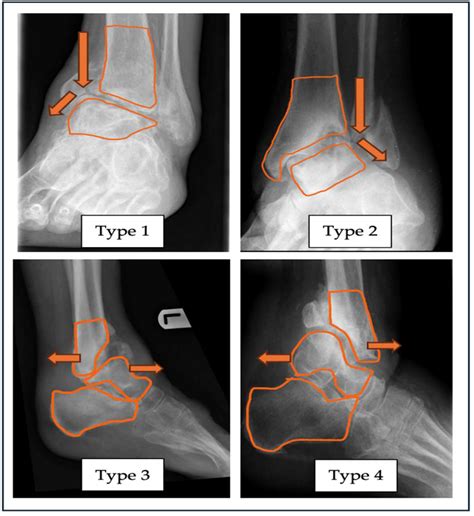

Imaging studies are essential for confirming the diagnosis and assessing the extent of the condition. Common imaging studies include:

• X-rays: To visualize bone structure and detect any fractures or deformities

Stages of Charcot Arthropathy Foot

Charcot arthropathy foot is typically divided into three stages based on the severity of the condition:

Stage Description

Stage 0 Pre-Charcot: Early signs of inflammation and bone resorption without visible deformities

Stage 1 Development: Active inflammation and bone resorption leading to joint destruction and deformities

Stage 2 Coalescence: Inflammation subsides, and the bones begin to fuse together, stabilizing the foot

Stage 3 Consolidation: The foot is stable, but deformities may persist, and the risk of ulceration and infection remains

Understanding the stage of Charcot arthropathy foot is crucial for determining the appropriate treatment plan.